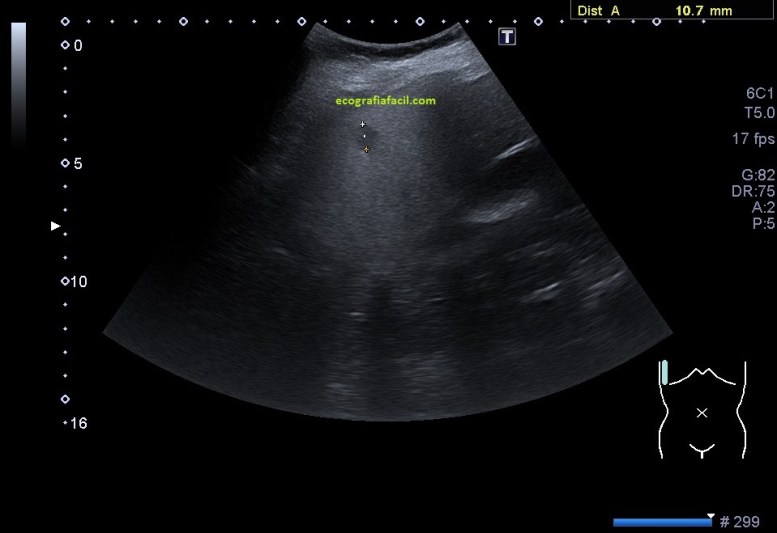

La LOE fue estudiada de manera protocolaria, haciendo medidas y aplicándose el Doppler, en este caso el modo angio o doppler power.

Esta LOE podría ser estudiada a modo de ampliación de estudio con 2 técnicas, la Ecografía de Contraste y/o la RMN a criterio de la Radióloga. Te enlazo con Post donde puedes repasar el uso de este contraste en un nódulo hepático.

Si se estudiase con contraste ecográfico, la respuesta de esta lesión debiera ser:

REALCE COMPLETO HOMOGÉNEO (rueda de carro) en fase arterial + HIPER o ISO (lavado lento) en fase portal + ISO o HIPER en fase tardía, mayoritariamente isoecogénica.